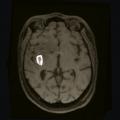

• un abcès cérébral (fig. 4) en présence d’un syndrome fébrile, d’un foyer infectieux, en particulier quand la prise de contraste est annulaire, un tuberculome en cas de contage ou terrain à risque ;